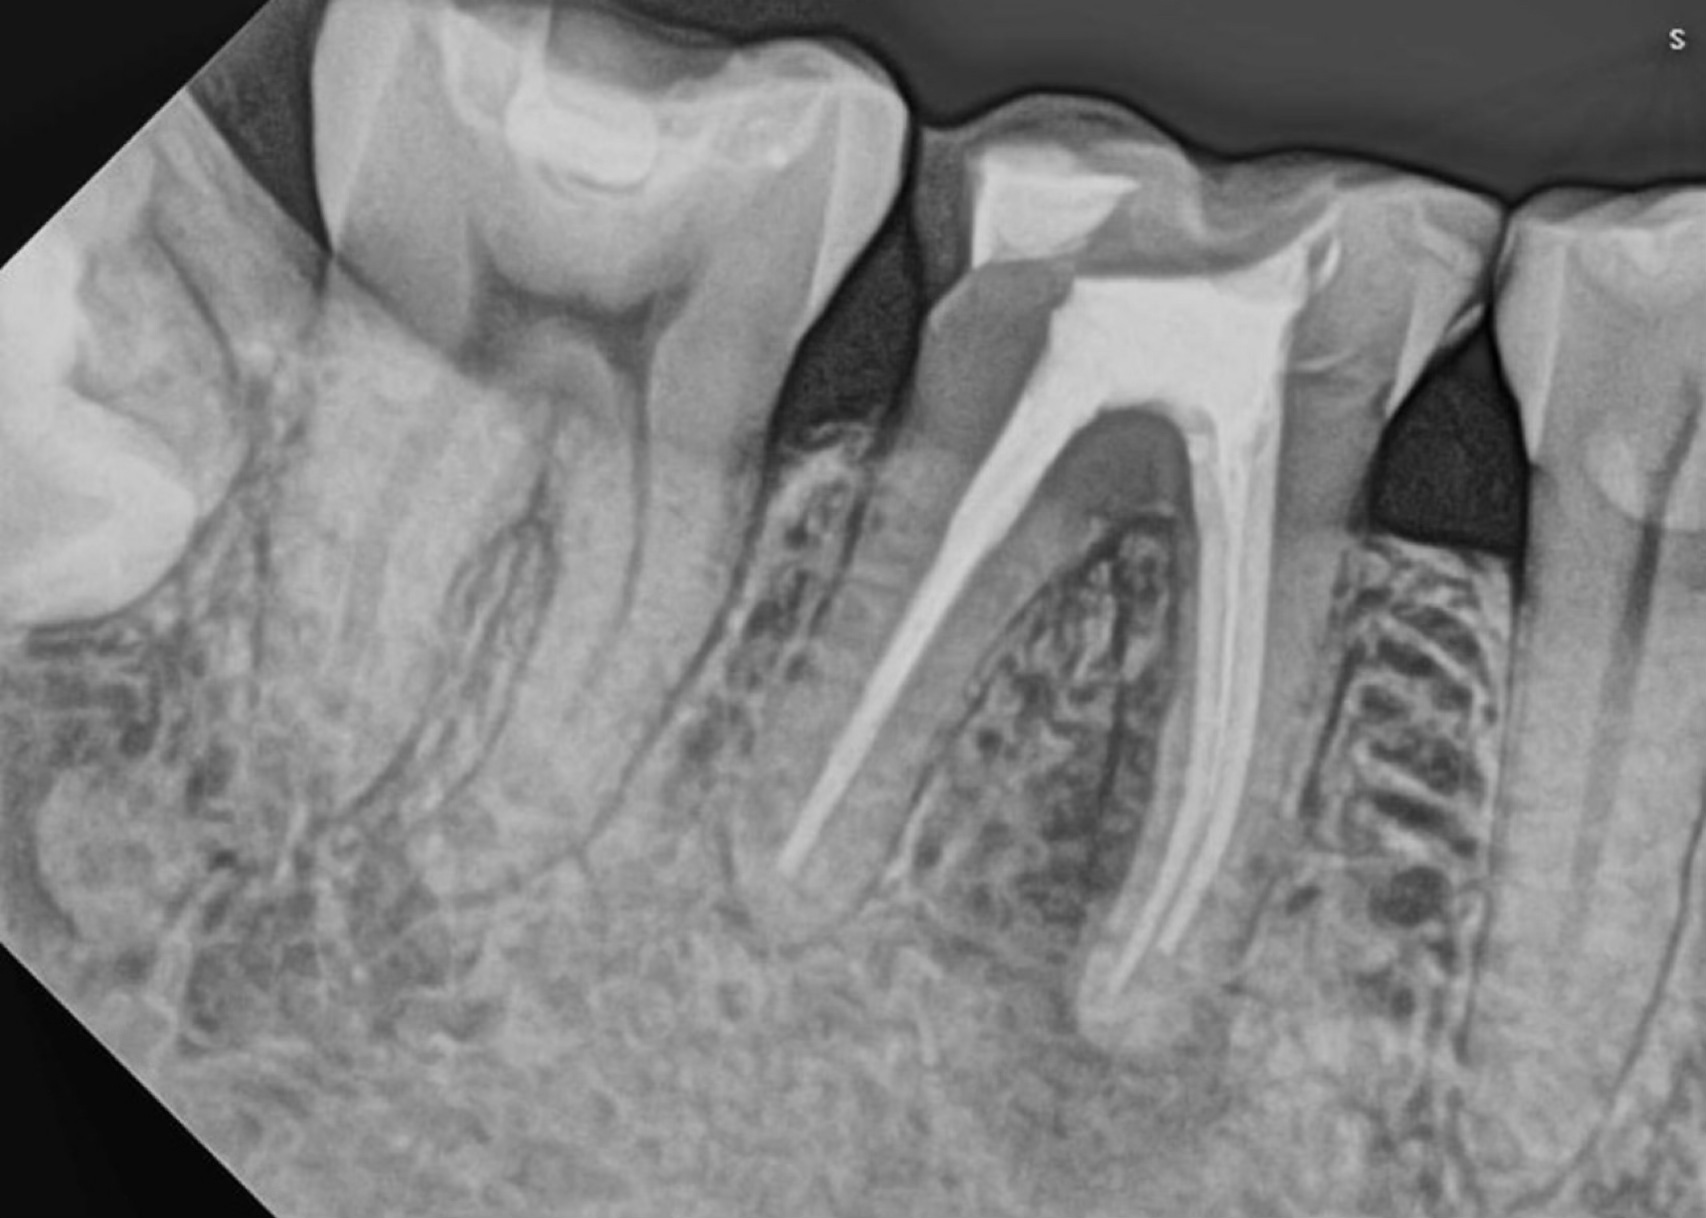

Tooth #11 with a calcified canal following traumatic injury